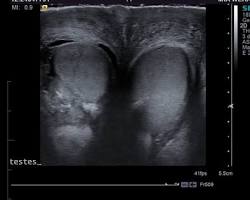

- To diagnose testicular problems: This could include conditions such as orchitis (inflammation of the testicles) or hydrocele (fluid collection around the testicles).